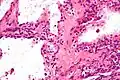

Micrograph showing a pancreatic serous cystadenoma. H&E stain. | |